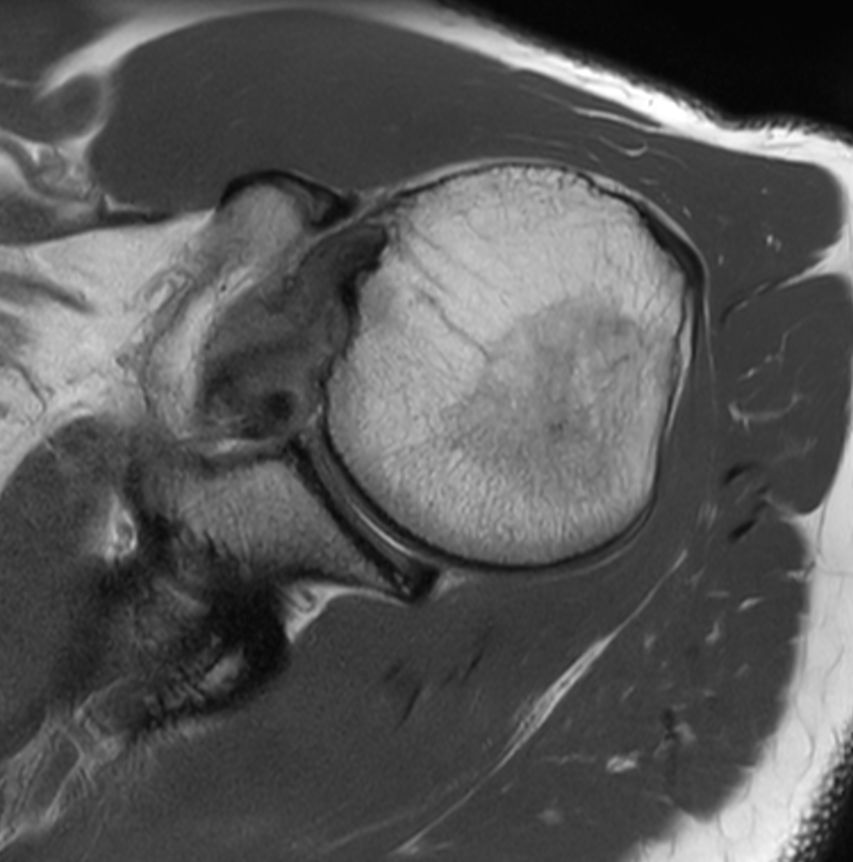

Shoulder with the dS Shoulder 16ch coil

University of Vermont Medical Center, Burlington, USA